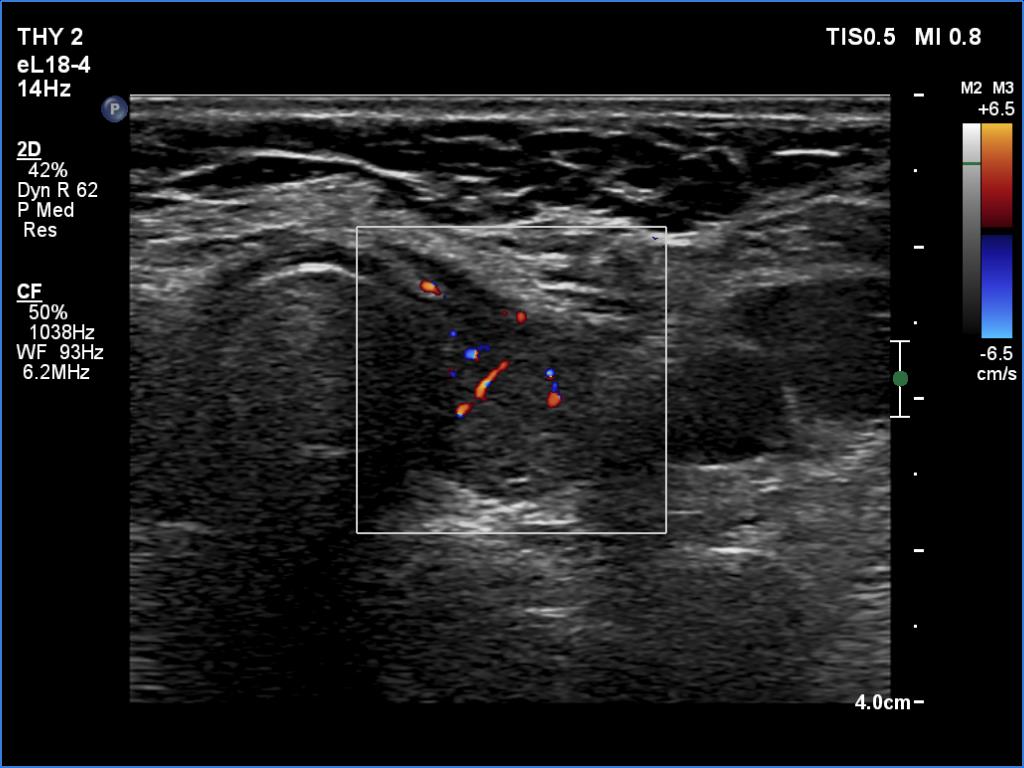

Lymphocytic thyroiditis - case 897

Examination one

Six month later

Focal form of lymphocytic thyroiditis is presented. At the first examination, beside smaller hypoechoic areas, the left lobe had a larger discrete lesion. It was doubtful whether this should be regarded as pathological nodule or not. In the first case, the lesion is an EU-TIRADS 5 nodule due to the irregular margins while in the latter, this is an EU-TIRADS 1 lesion. Six months later, the lesion had virtually disappeared which means that this was not a true nodule.